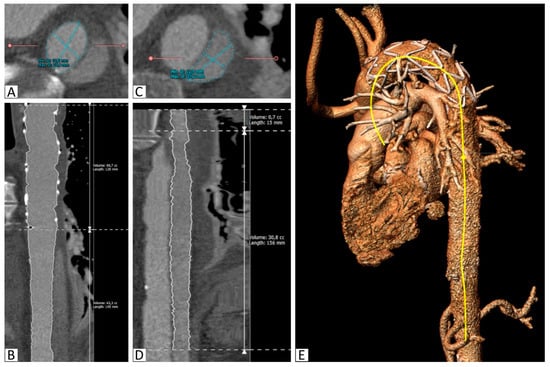

Areas of the TL were measured at the proximal and distal end of the stent graft and at the level of the celiac trunk (Figure 1).

Volume measurements of the TL and the PFL at the stent graft level (S1), between the stent graft and celiac trunk (S2), and the total thoracic aorta (S1+S2) were taken.

The angle between the aortic arch (measured at the most cranial point of the arch) and the distal end of the stent graft was measured on the created 3D model. All of the measurements were obtained independently by two observers (Figure 1 and Figure 2).

Figure 2.

Segmentation of the aorta with the implanted stent. (A): Segmentation of the true lumen in the descending thoracic aorta distal to the stent graft on a reconstructed slice orthogonal to the vessel, (B): Curved multiplanar reconstruction of the true lumen between the proximal stent graft and the celiac trunk, including length and volume calculations, (C): Segmentation of the false lumen in the descending thoracic aorta distal to the stent graft on a reconstructed slice orthogonal to the vessel, (D): Curved multiplanar reconstruction of the false lumen between its origin in the stent graft and the celiac trunk, including length and volume calculations, (E): 3D reconstruction with the semiautomatically created center-line (yellow).